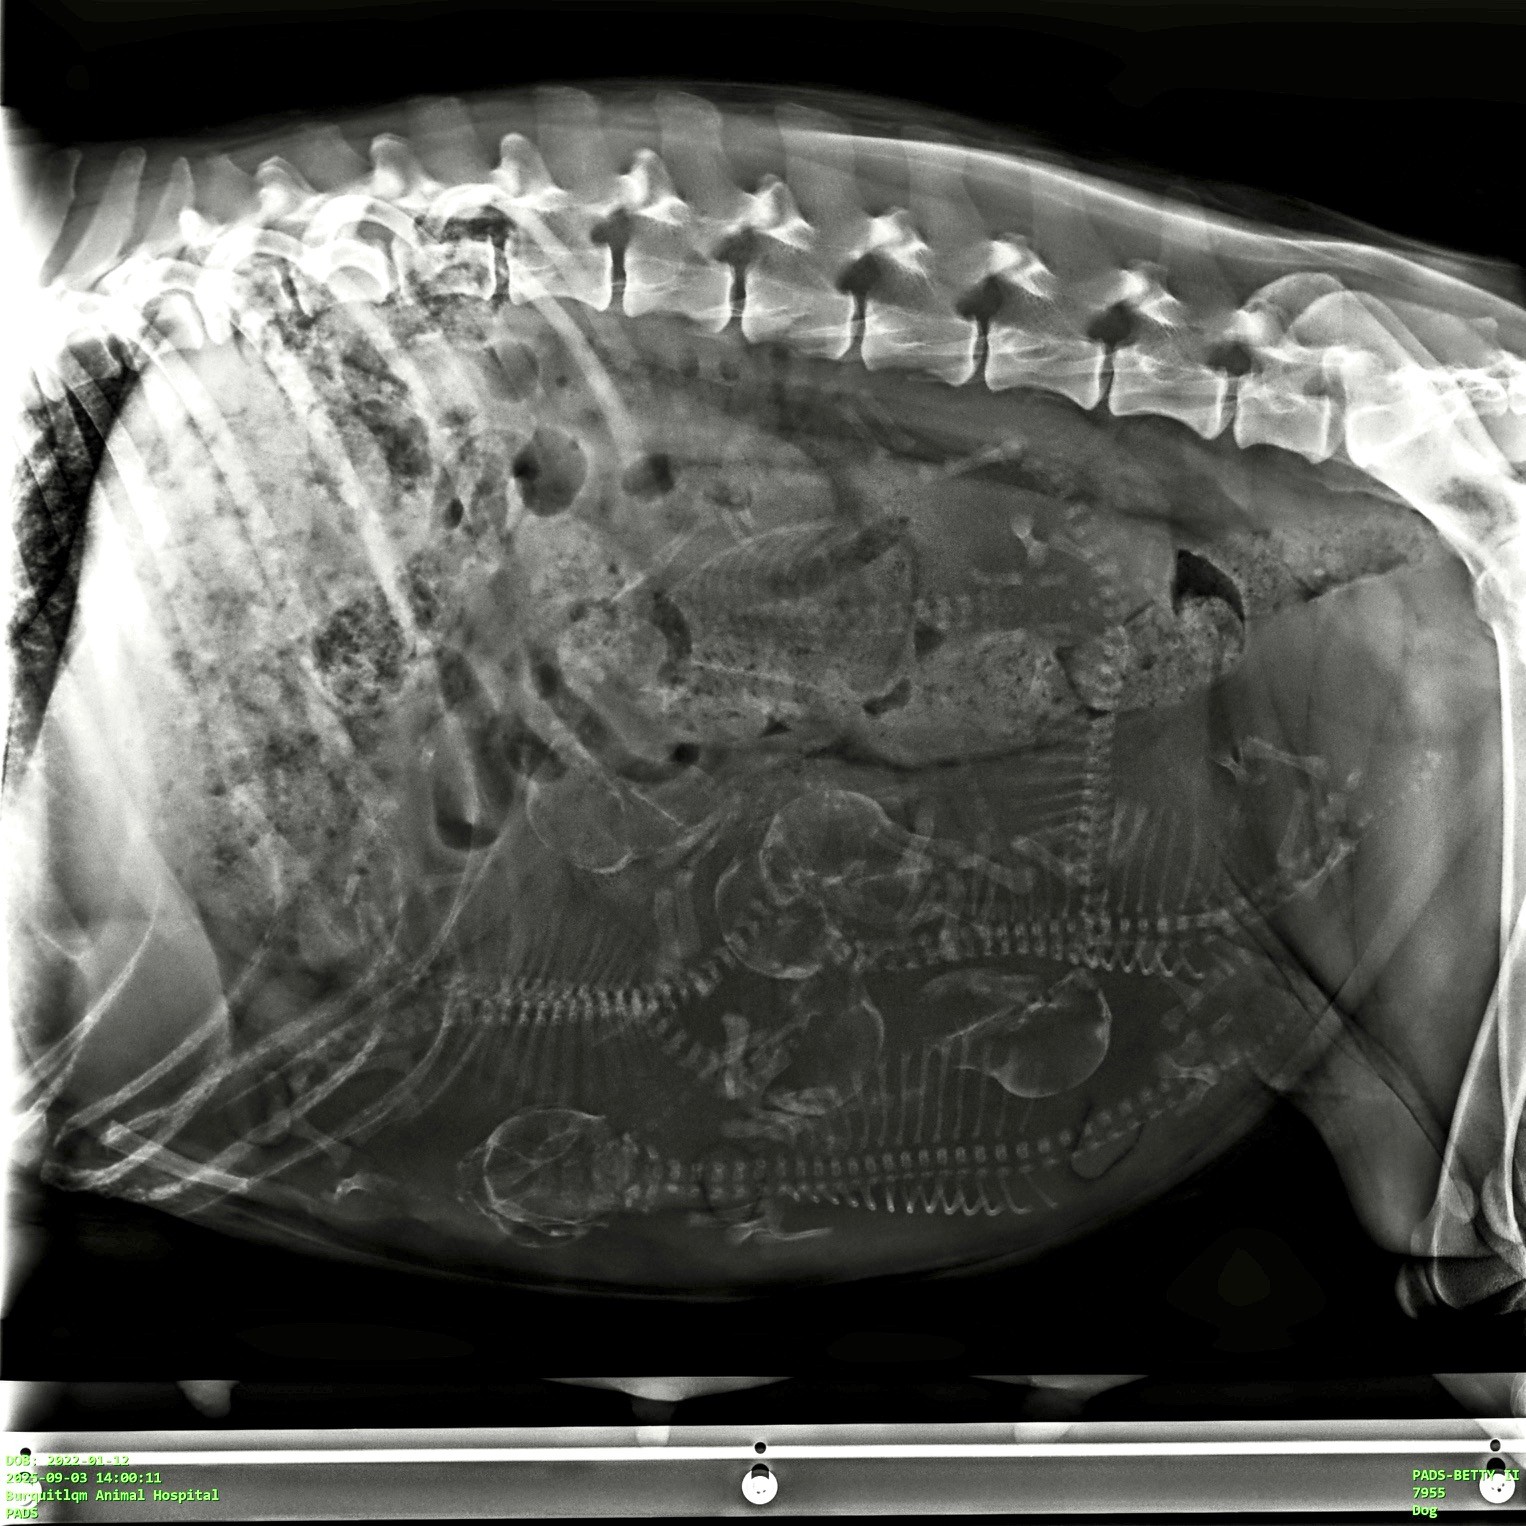

I was thrilled to welcome Betty back to the house in mid-August to have her 3rd litter. We did lots of walks and swims to make sure she was in tip-top shape for delivery. And on September 8th, she presented with 6 beautiful healthy puppies – right on her due date!